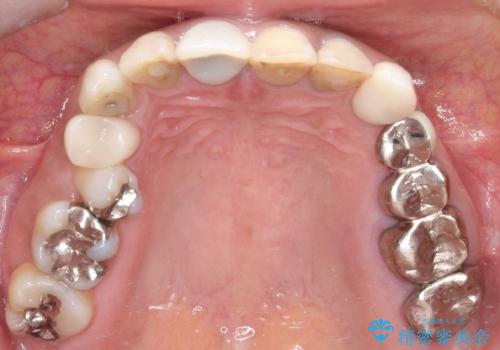

- 前歯の変色を主訴に来院されました。

歯茎のラインも整っていなかったため、手術を行いきれいな被せ物をいれることができました。

歯茎のラインを整える手術を行ったあとは、しばらく待ってから被せ物の治療を行っていきます。